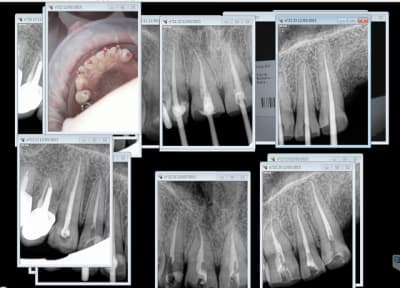

Pas fiable hein ? désolé pour ces traitements de merde, mais en 45 mn avec des tarifs opposables de merde, j'ai pas le temps de fignoler. -)))

Capture d e cran 2015 03 12 11.34 - Eugenol

Image saznoz - Eugenol

Dis moi chicot29, ( désolé, rien à voir avec le sujet) mais pourquoi toutes les dents ont été devitalisées?...je ne vois pas ni caries ni délabrements.

Merci de ta réponse.

Sinon, très belles endos.

Disons qu'au vu des prestations sécu et mutuelles défoncer les ratiches est la seule solution économiquement viable.

Cas chiant d'ailleurs au vu des usures des bords incisifs, je m'en serais bien passé !

Mais que se passe t il dans ce type de cas en cas de contrôle secu, avec radio avant endo?

C est litigieux ou pas?

Je pense que certain DC te diront ok....et d'autres pas ok, non??

Ben figures toi que le " dentiste conseil" de la mutuelle a demandé les radios à la patiente + les photos et a accepté de rembourser.

Appareils à refaire au fond pour augmenter la DV en plus.